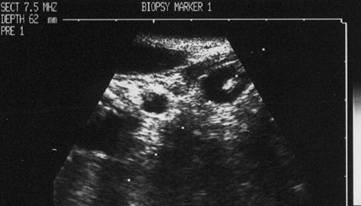

CITOaspiratIA ecogHIDATA

Noduli chistici

Femeie de 51 ani. Nodul in lobul drept, marcant hipoecogen, cu margini rau definite, cu ecouri in interior si microcalcificari.

Imaginea dupa insertia acului.

Varful acului este in centrul leziunii. Examenul citologic: leziune benigna.